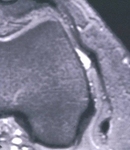

Impingement zone occurring at around 30° of knee flexion

From the personal collection of Dr J.C. Mak